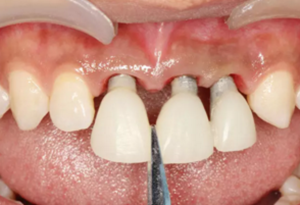

(2)即刻種植、即刻臨時修復(fù)。術(shù)中不翻瓣微創(chuàng)拔除牙根,牙槽 窩骨壁完整。在多級導(dǎo)板輔助下完成種植窩洞制備,植入Bego柱形種植 體,型號分別為:上頜右側(cè)中切牙位點4.1mm×15mm、上頜左側(cè)中切牙 位點?3.75mm×15mm、上頜左側(cè)側(cè)切牙位點3.25mm×15mm,扭矩均為 35N·cm。種植體與唇側(cè)骨壁間隙約2mm,植入Bio-Oss®Collagen骨膠 原。戴入橋用鈦臨時基臺,臨時冠就位順利,自凝樹脂口內(nèi)粘接后適當(dāng)修整 外形,充分磨光,調(diào) 至正中 、前伸 和側(cè)方 與對頜牙均無接觸。術(shù)后 根尖片顯示種植體位置、方向良好。

(3)軟組織成形。術(shù)后4個月復(fù)查,臨時修復(fù)體完好,軟組織色粉、 質(zhì)韌、點彩清晰,齦緣位置基本穩(wěn)定,齦乳頭區(qū)可見三角間隙。此后1個月內(nèi),先后2次取下臨時冠,用樹脂調(diào)整修復(fù)體頸部外形,進行軟組織成形。 術(shù)后6個月復(fù)查,軟組織形態(tài)滿意、位置穩(wěn)定,進行最終修復(fù)。

(4)最終修復(fù)。種植體周圍軟組織改建成熟以后,進行最終修復(fù)。本 病例采用兩步法印模技術(shù)精確記錄種植體的三維位置和種植體周圍軟組織穿 齦輪廓外形。 首先,口內(nèi)制取臨時冠及周圍軟硬組織的硅橡膠陰模,復(fù)制軟硬組織 表面形態(tài)。然后,取下臨時修復(fù)體,常規(guī)制取閉窗式種植體水平聚醚印模, 精確記錄種植體的三維位置,灌制含人工牙齦的超硬石膏模型。最后,去除 模型上的人工牙齦,將臨時修復(fù)體戴入到模型上,在臨時修復(fù)體周圍和硅橡 膠陰模內(nèi)注入人工牙齦,將陰模就位到含臨時冠的石膏模型上,精確轉(zhuǎn)移穿齦輪廓外形,獲得工作模型。 制作螺絲固位的一體化氧化鋯基臺冠,以切削方式制作完成后,表面 添加飾瓷來獲得理想的美觀效果。 術(shù)后7個月,戴入最終修復(fù)體,紅白美學(xué)效果滿意。

圖15 調(diào)整臨時修復(fù)體外形

圖16 軟組織成形后口內(nèi)像